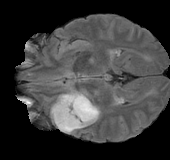

As we observe from the right image in Fig. 2, our BRM, both from MIMO and SISO settings, predicts the performance of dedicated models with a high correlation. We further choose the best three , and perform the last stage of fine-tuning accordingly to (6). A visual evaluation on real data is shown in Fig. 3. For simulated data, please refer to the Supplemental Material section.

Base on the best performing , we perceive that among , , and FLAIR, the results are best when is sampled the most. We suggest that this makes intuitive sense as images provide the best contrast out of the three sequences, which can compensate for the details lost in other images. The same observation can be made on the simulated data, where both and FLAIR show good contrast. When the time setting is changed to non-uniformity, we can see that our search for the best sampling strategy reflects the change. is sampled more as a result of faster acquisition time, while is still sufficiently sampled.

| Sequence | LR | SISO | MIMO | MIMO tuned | GT |

|---|---|---|---|---|---|

(a) 34.38/0.9371

(a) 34.38/0.9371

|

(b) 42.42/0.9883

(b) 42.42/0.9883

|

(c) 44.60/0.9920

(c) 44.60/0.9920

|

(d) 45.50/0.9940

(d) 45.50/0.9940

|

(e) PSNR/SSIM

(e) PSNR/SSIM

|

|

(f) 29.74/0.8903

(f) 29.74/0.8903

|

(g) 36.25/0.9734

(g) 36.25/0.9734

|

(h) 36.42/0.9752

(h) 36.42/0.9752

|

(i) 37.70/0.9832

(i) 37.70/0.9832

|

(j) PSNR/SSIM

(j) PSNR/SSIM

|

|

(k) 39.89/0.9311

(k) 39.89/0.9311

|

(l) 43.94/0.9864

(l) 43.94/0.9864

|

(m) 44.74/0.9883

(m) 44.74/0.9883

|

(n) 45.49/0.9894

(n) 45.49/0.9894

|

(o) PSNR/SSIM

(o) PSNR/SSIM

|